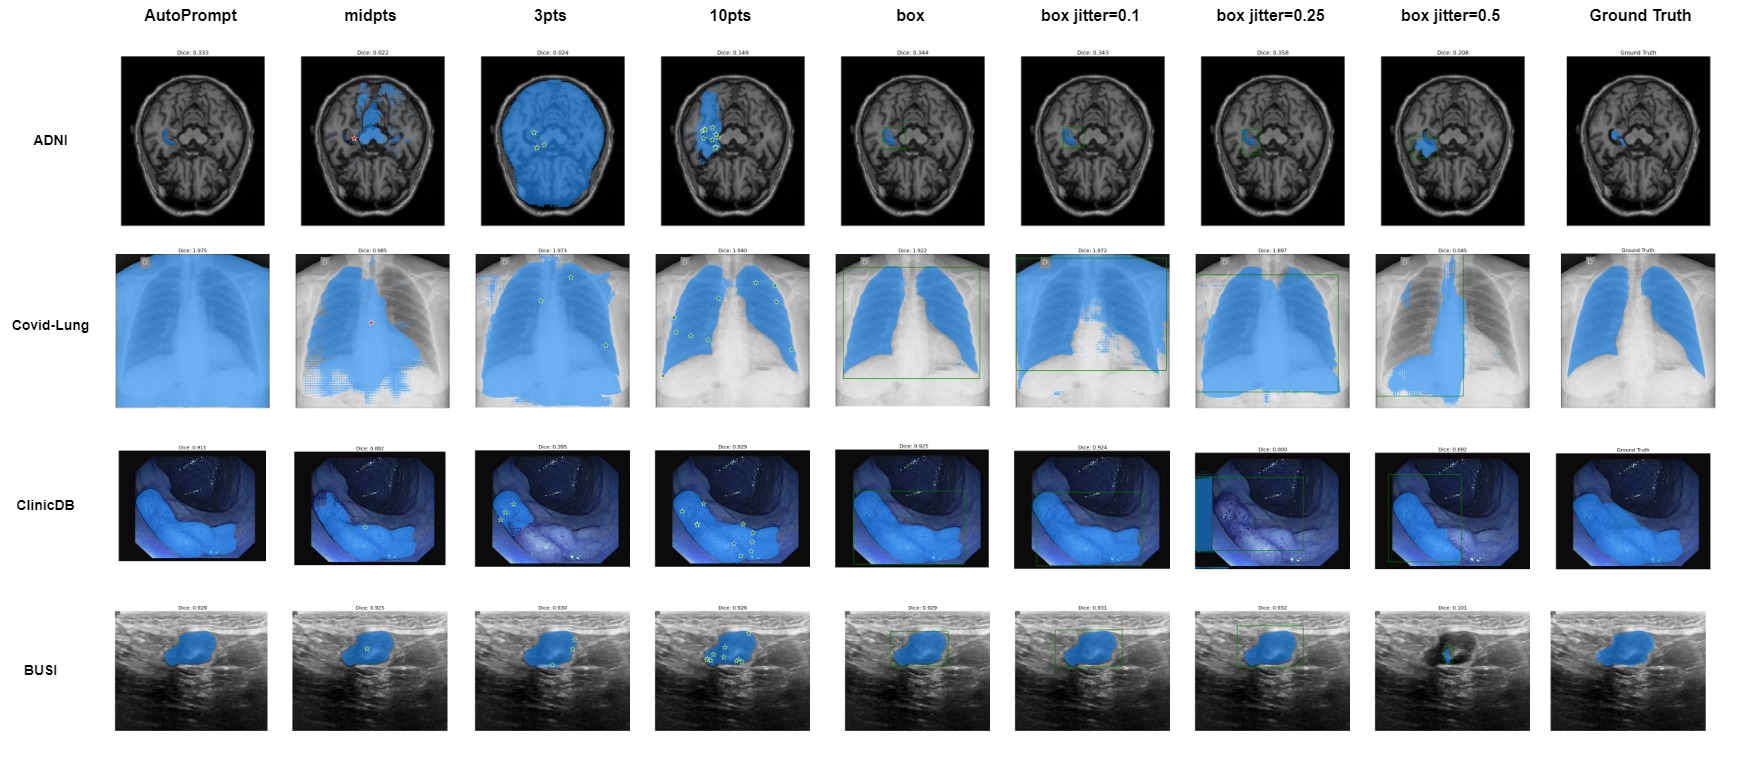

As shown in Table I, II, and Fig 1, the performance of SAM varies among different datasets and prompt modes. Specifically, the box-prompt mode with zero jitters is the best way to utilize the SAM model on medical image tasks. The box-prompt mode achieves the highest average dice compared with the other two modes. This prompt method also occasionally gives results that are close to the SOTA methods. Thus we argue that box-prompt mode might be the most suitable prompt method to leverage the SAM model in medical image segmentation tasks. In General, the Dice of the SAM model with box-prompt mode is 0.

In Fig 2, we show how the prediction accuracy would change after more jitters are applied in all datasets .one can tell that the jitters added to the boxes can significantly affect the prediction mask accuracy. We discussed this observation before. We also give a visualization of some segmentation results in Fig 3.